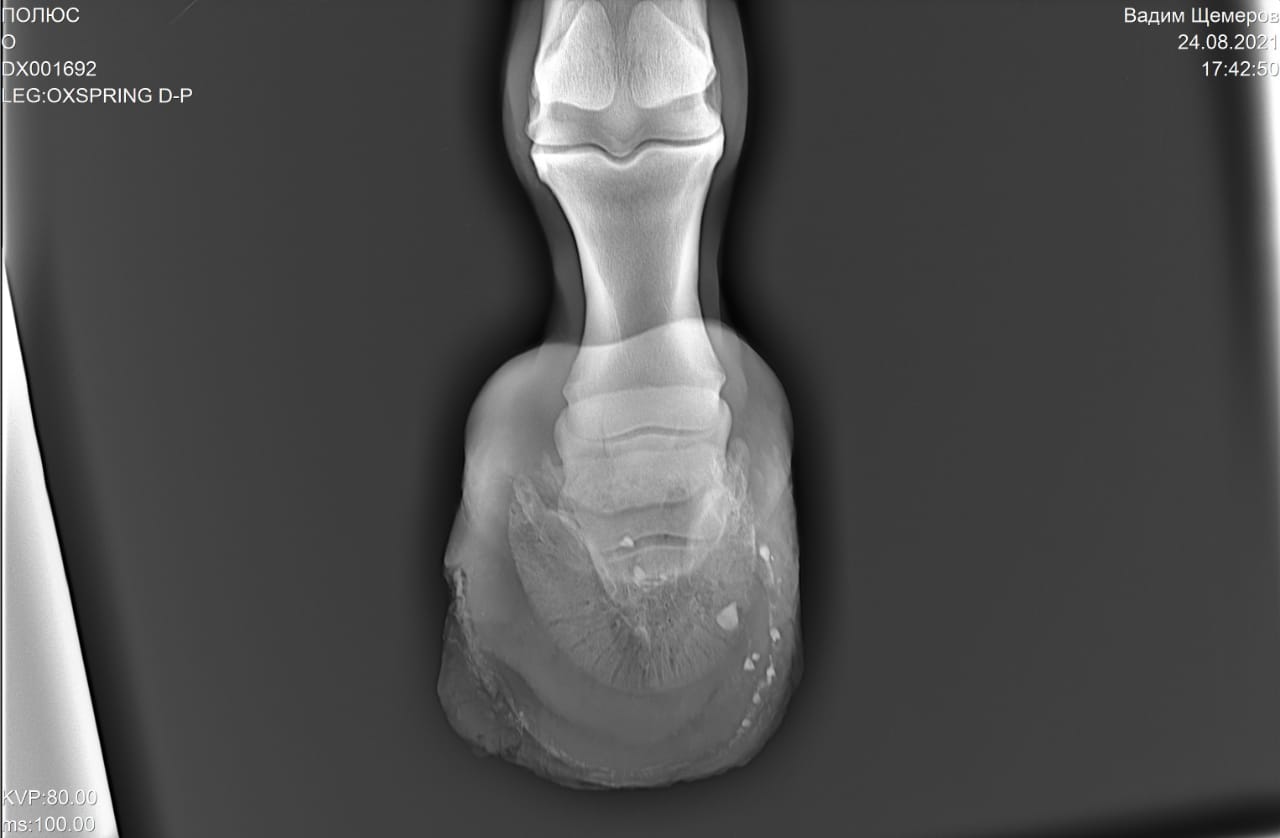

2) Старый перелом и изменение конфигурации края челночной кости с переостальной реакцией этого края.